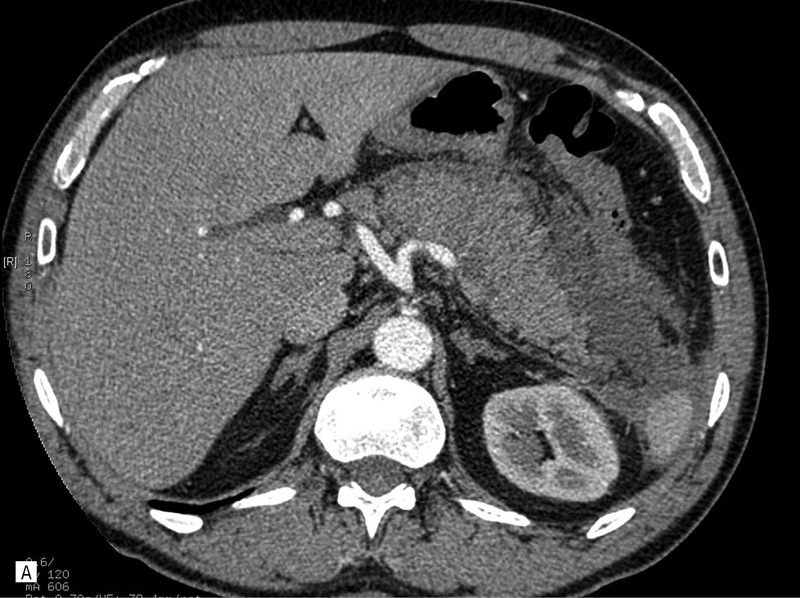

55-letni mężczyzna został przyjęty na oddział chirurgiczny z powodu silnych bólów brzucha, wymiotów i zaburzeń oddawania stolca – objawów sugerujących ostre zapalenie trzustki. W badaniach laboratoryjnych potwierdzono rozpoznanie. Wykonano badanie USG, które ujawniło powiększenie trzustki i zatarcie jej echostruktury. Pełną ocenę utrudniało napięcie powłok brzusznych, obrzęk krezki oraz obecność gazu w rozdętych pętlach jelit. Wykonano dwufazowe badanie TK, które potwierdziło obecność obrzękowej postaci zapalenia trzustki. Nie stwierdzono wówczas płynu w jamie otrzewnej. Śladowa ilość płynu była widoczna w lewej jamie opłucnowej (ryc. 1).

Rycina 1. Badanie TK w ostrej fazie zapalenia trzustki. A. Przekrój poprzeczny. Widoczne znaczne poszerzenie trzustki (obrzęk) z obecnością nacieku zapalnego w otaczającej tkance tłuszczowej, penetrującego wzdłuż naczyń w kierunku widocznej fragmentarycznie (biegun przedni) śledziony. B. Przekrój czołowy. Widoczna niepowiększona śledziona. Cechy nacieku zapalnego w okolicy przedniego bieguna. Bez cech nacieku i przestrzeni płynowych w otoczeniu nerek i mięśni biodrowo-lędźwiowych.